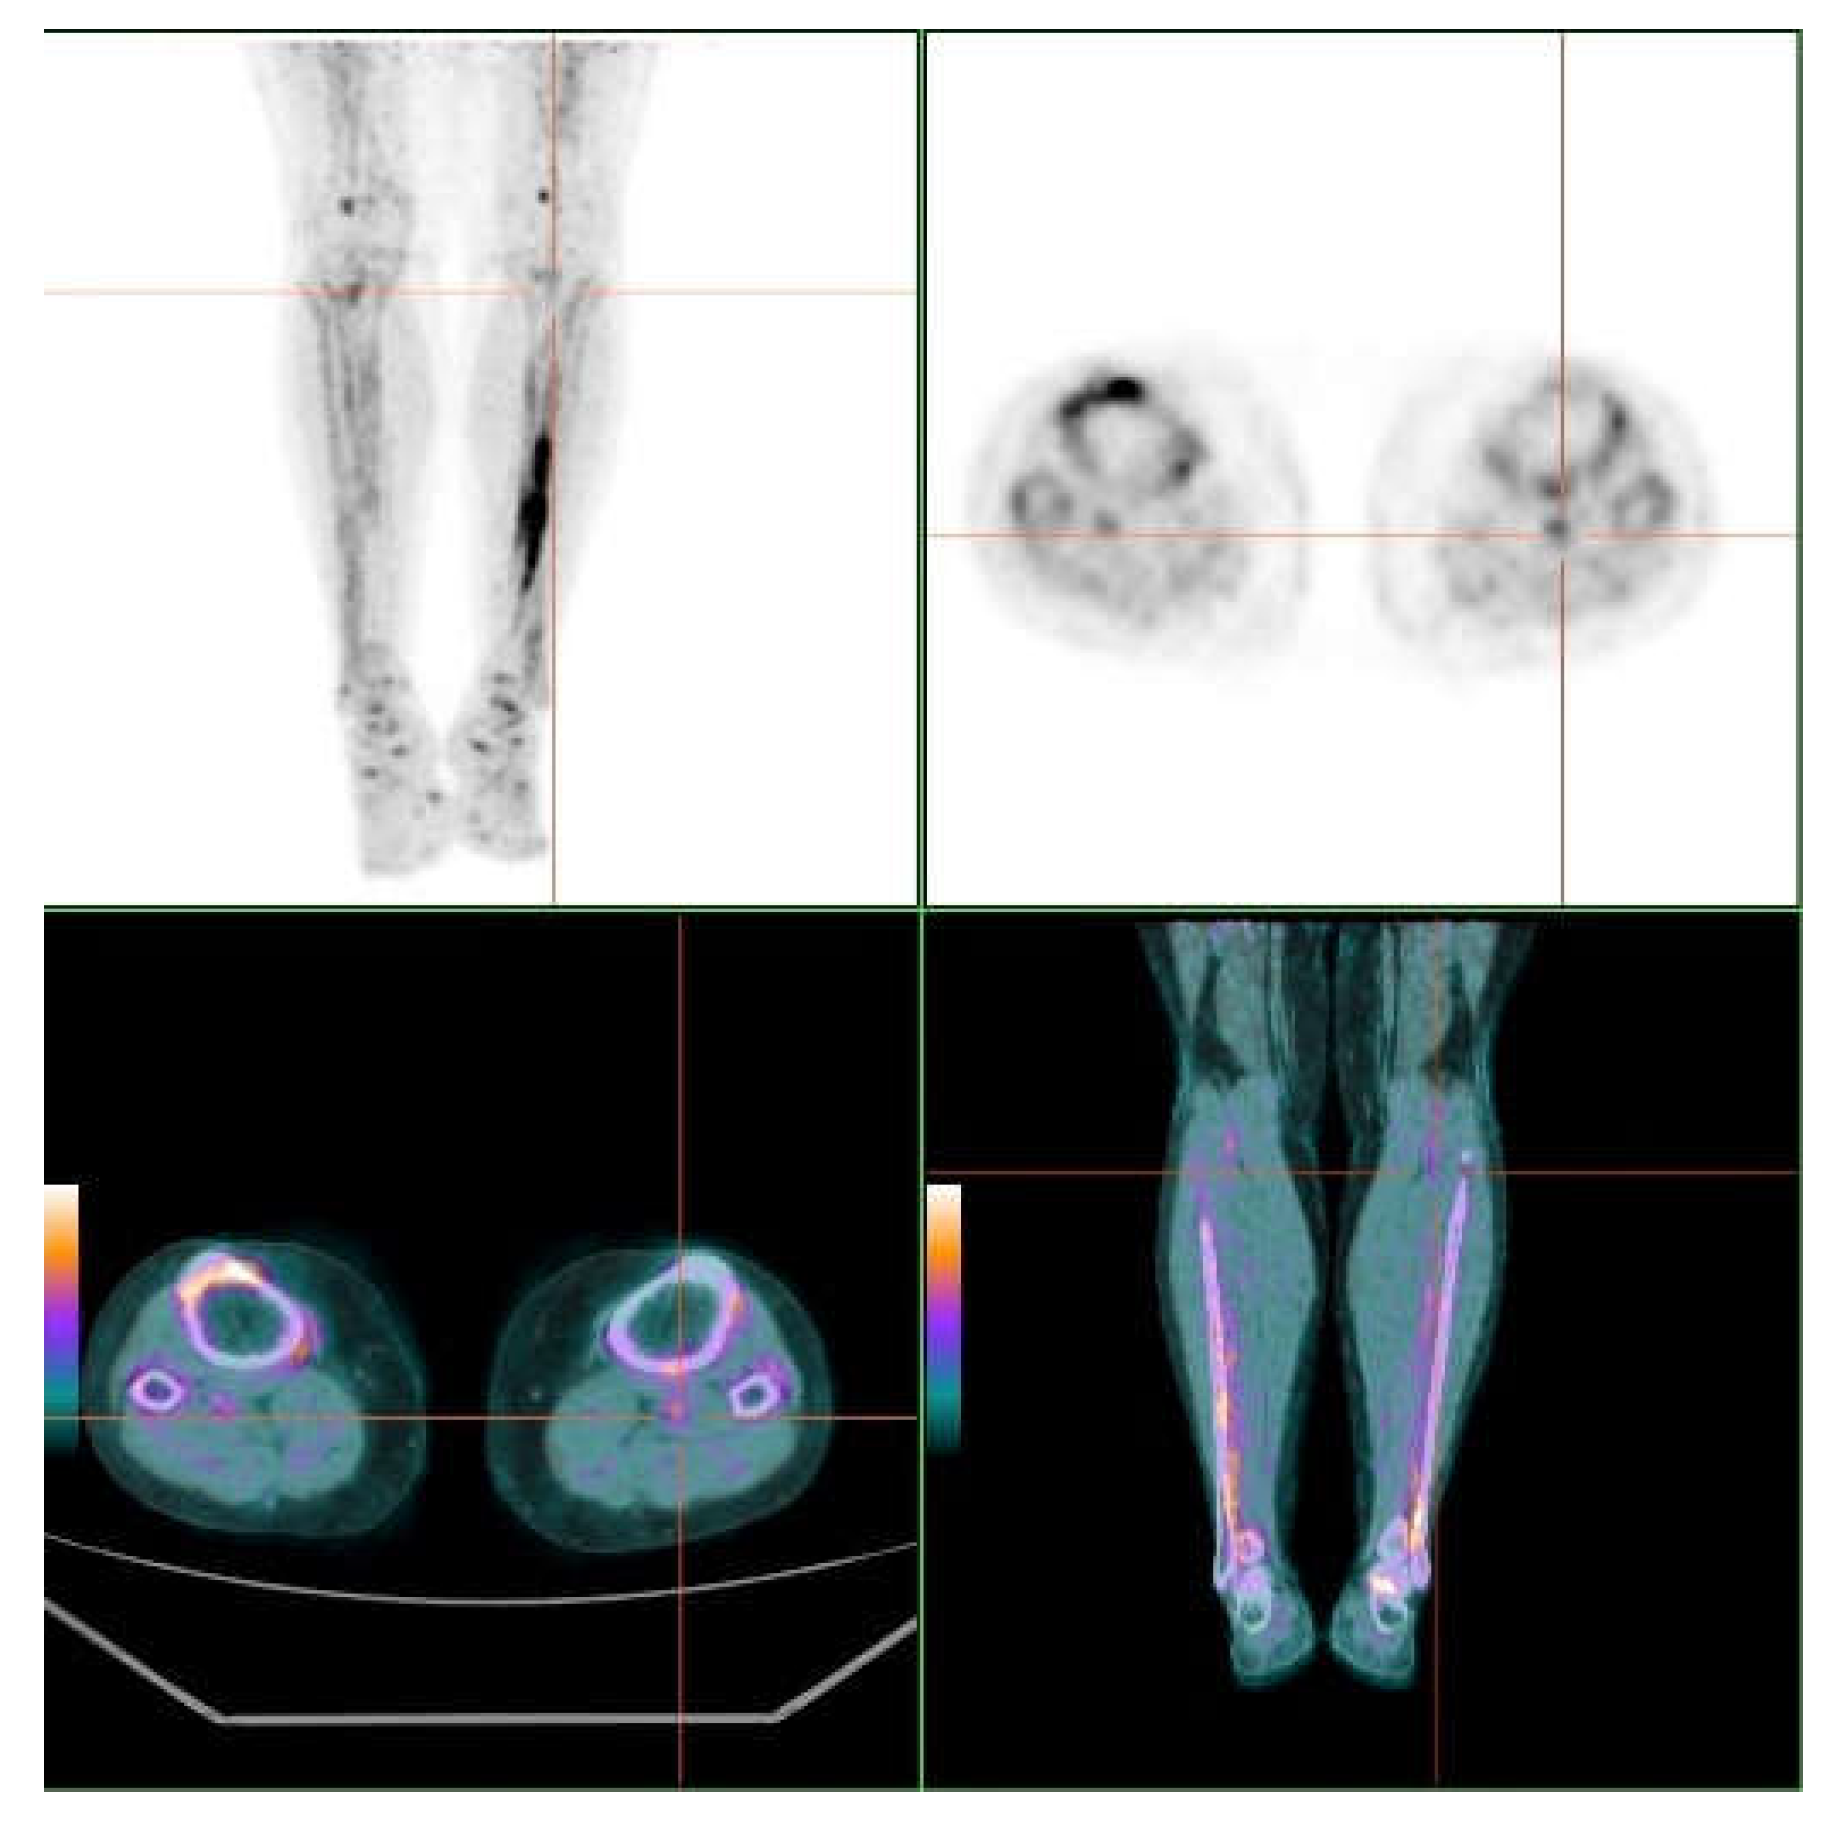

3.2. Skin and Vascular Uptake of 18F-NaF